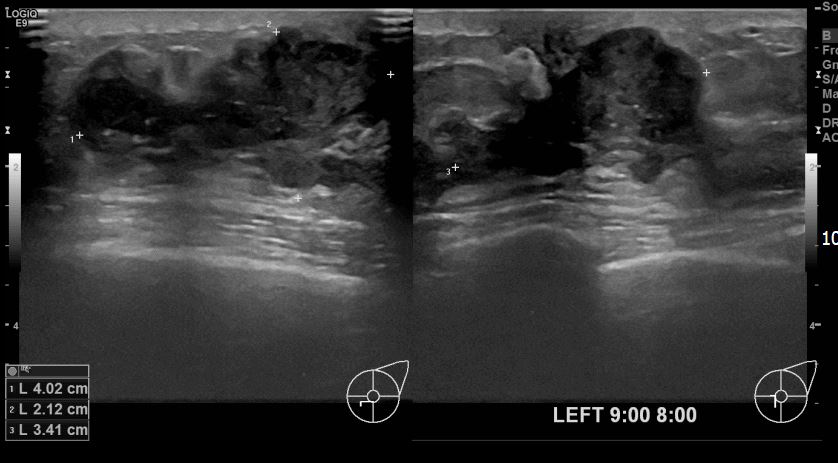

아산유외과개원후 719번째 유방암진단

상기환자 좌측유방멍울만져지고 통증있어 내원하신 30대 여성분으로 유방암 의심혹 조직검사 시행 후 유방암 진단되었습니다.